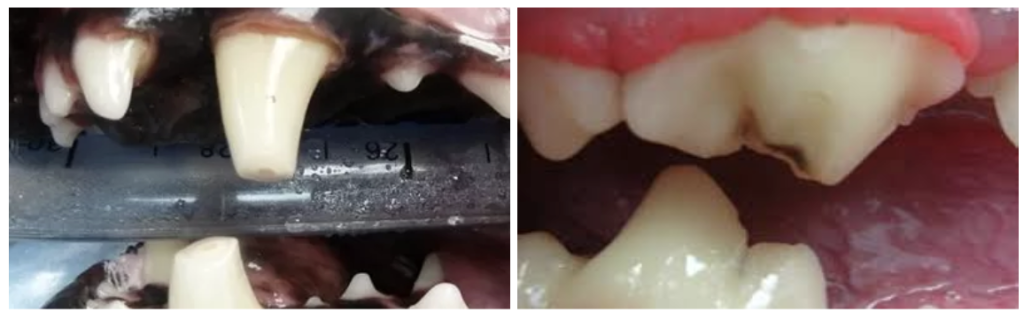

寵物牙科 – 根管治療情況2:牙齒磨損、磨耗

「磨損」及「磨耗」兩種看似字面意思近似,但其實是有差別的唷!在牙齒磨損或磨耗的情況下,如果磨損嚴重至牙髓裸露時,則需進行「根管治療」或是「拔牙」。

- 牙齒磨損(abrasion):因啃咬堅硬外物如金屬籠、球、骨頭等,造成牙釉質與牙本質逐漸磨損。

- 牙齒磨耗(attrition):因牙齒咬合不正,或是正常的咀嚼造成的磨耗,導致牙釉質、牙本質漸漸消耗。

圖片來源:https://www.veterinarydentalcenter.com/oral-conditions/tooth-fracture/worn-tooth/